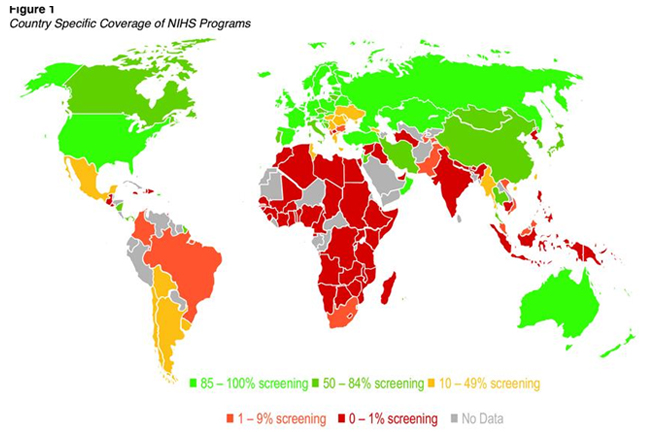

A newborn may look healthy at birth, and clinical examination may appear normal. However, some rare genetic, endocrine, and metabolic conditions may be present. If not detected early, delayed treatment can lead to severe consequences such as neurodevelopmental delays and, in extreme cases, even death. Newborn screening is a universal public health program, widely accepted and practiced in developed countries, aimed at reducing mortality and morbidity in newborns.

Newborn screening identifies conditions that can affect a child’s long-term health or survival. Early detection, diagnosis, and intervention can prevent death or disability, enabling children to reach their full potential.